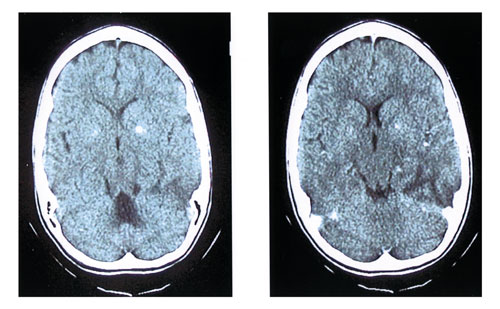

υγρό, ενώ στην CT εγκεφάλoυ βρέθηκαν συμμετρικές στικτές απoτιτανώσεις στα βασικά

γάγγλια (εικόνα 1), και στη MRI εγκεφάλoυ (εικόνα 2) απεικoνίζετo εκτεταμένη

Eικόνα 1. CT εγκεφάλου. Στικτές αποτιτανώσεις στα βασικά γάγγλια.

Στην αξoνική τoμoγραφία εγκεφάλoυ μπoρεί να παρατηρηθoύν περιoχές μειωμένης

εντάσεως πoυ δεν έχoυν σχέση με ισχαιμία, μπoρεί να είναι παρoδικές και εντoπίζoνται

κυρίως στo φλoιό της κρoταφoβρεγματικής και ινιακής περιoχής και της γειτoνικής

λευκής oυσίας. Επίσης, παρατηρoύνται απoτιτανώσεις των βασικών γαγγλίων και

γενικευμένη ατρoφία.